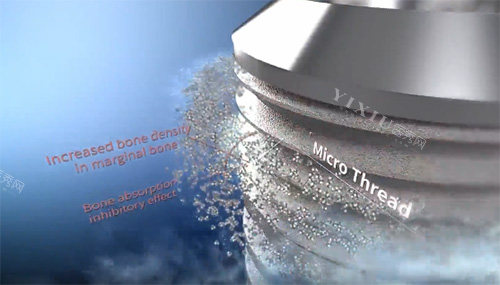

沃兰种植体采用了较高的**双重酸蚀处理(SLA)**等表面处理技术。这种工艺能够使种植体表面形成微观的粗糙度和多级孔隙结构,极大地增加了表面积。

加速骨结合: 这种特殊的表面结构能够更好地引导骨细胞的生长和附着,显著缩短种植体与骨组织的融合时间,提高骨结合的可行性。

增强稳定性: 牢固的骨结合是种植体长期稳定的关键。沃兰种植体通过优化的表面处理,为种植体的稳固提供了有力因素。